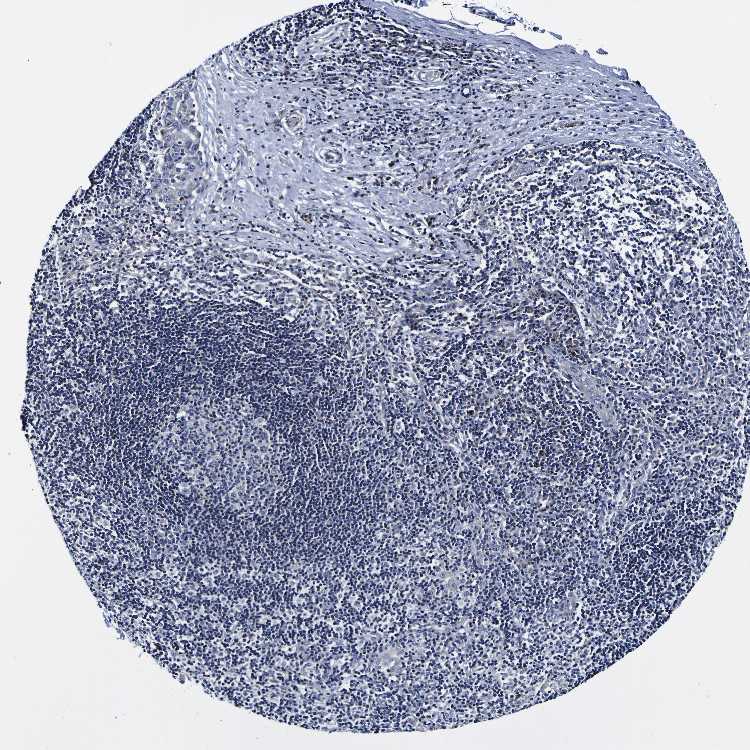

SOFT TISSUE 1 - Antibody stainingi

Antibody staining in the annotated cell types in the current human tissue is reported as not detected, low, medium, or high, based on conventional immunohistochemistry profiling in selected tissues. This score is based on the combination of the staining intensity and fraction of stained cells.

Each image is clickable and will lead to virtual microscopy that enables deeper exploration of all samples and also displays staining intensity scores, fraction scores and subcellular localization as well as patient and tissue information for each sample.

Antibody HPA011912

Chondrocytes Low

Fibroblasts Not detected